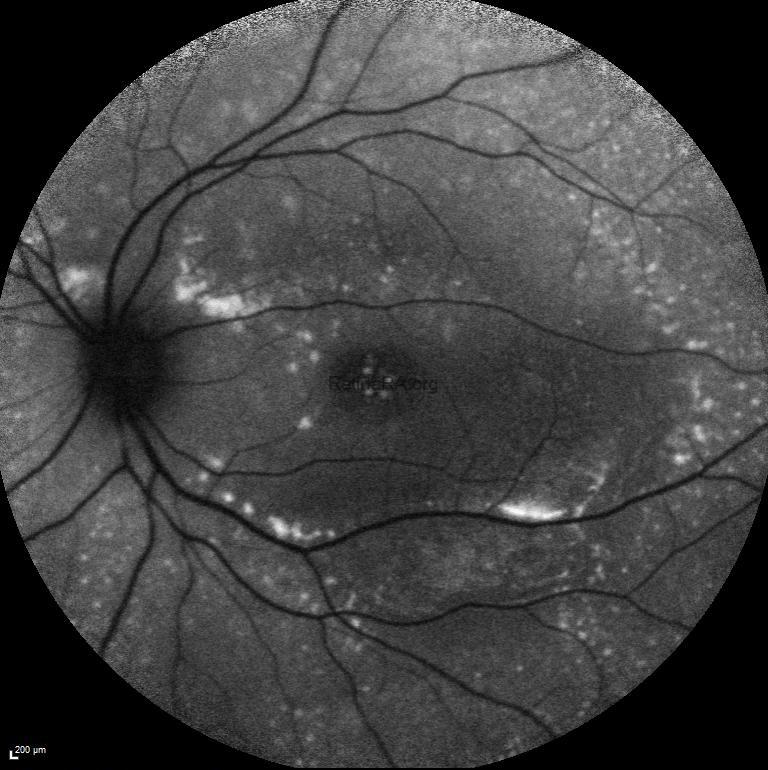

Fundus autofluoresce imaging demonstrated widespread hyperfluorescent foci corresponding to the subretinal deposits in both eyes.